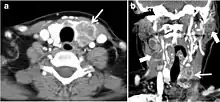

Thyroid lymphoma represents about 5% of thyroid malignancies. Non-Hodgkin's lymphoma is the most common type and can be secondary to generalized lymphoma or a primary tumour. Primary thyroid lymphoma usually pre-exists with Hashimoto's thyroiditis. On CT scans with and without contrast, lymphomas tend to have low attenuation values. Thyroid lymphomas have variable appearance and mostly manifest as a solitary mass (80%). They may also manifest as multiple nodules (15% to 20%) or as a bulky mass replacing the entire gland with extra-thyroid extension (Figs. 11 and and12).12). The presence of cervical lymphadenopathy supports such a diagnosis. Although it is uncommon, tumour necrosis has been reported.[1]

Fig. 11. Thyroid non-Hodgkin's large B-cell lymphoma in a 66-year-old female patient. an Axial enhanced neck CT scan demonstrates left thyroid lobe and isthmus homogeneously hypodense and minimally enhancing mass (white arrows). This lesion invades the prevertebral muscles (black arrows). Note the multiple enlarged level V lymph nodes (white arrowheads). b Post-treatment image shows significant reduction in size and mass effect of the left thyroid infiltrative mass, with almost complete resolution of the left cervical lymphadenopathy.[1]

Fig. 12. Diffuse thyroid large B-cell lymphoma in 79-year-old female patient. an Axial enhanced neck CT scan demonstrates a homogeneously hypodense and minimally enhancing large right thyroid solid mass (long white arrow) extending into the thyroid isthmus. It is encasing the right carotid artery (short white arrow) and displacing of the trachea and oesophagus to the left side.[1]